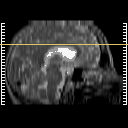

Stroke: proton density-weighted MR #2 -- Slice #17

[Home][Help][Clinical] Slice 17